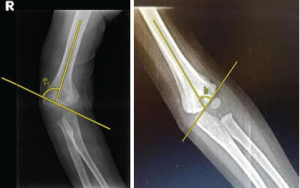

- Endobutton placement: A twin endobutton construct, consisting of two titanium buttons loaded with braided sutures, was used. The lower button was passed through the tunnels and toggled on the inferior surface of the coracoid. The fracture was reduced manually under direct vision, and the sutures were tensioned to achieve optimal alignment (Fig. 1 and 2).

4. Fixation and closure: Once the reduction was confirmed radiographically using fluoroscopy, the sutures were tied securely over the proximal button. The incision was closed in layers, and the arm was placed in a sling for immobilization.

The mean duration of surgery was 45 min (range 30–70 min), and the mean intraoperative blood loss was 90 mL (range 50–150 mL). Fluoroscopic imaging confirmed satisfactory reduction in all cases, with a mean residual displacement of 1.2 mm (range 0–3 mm) postoperatively. No intraoperative complications, such as neurovascular injury or technical failure, were reported.